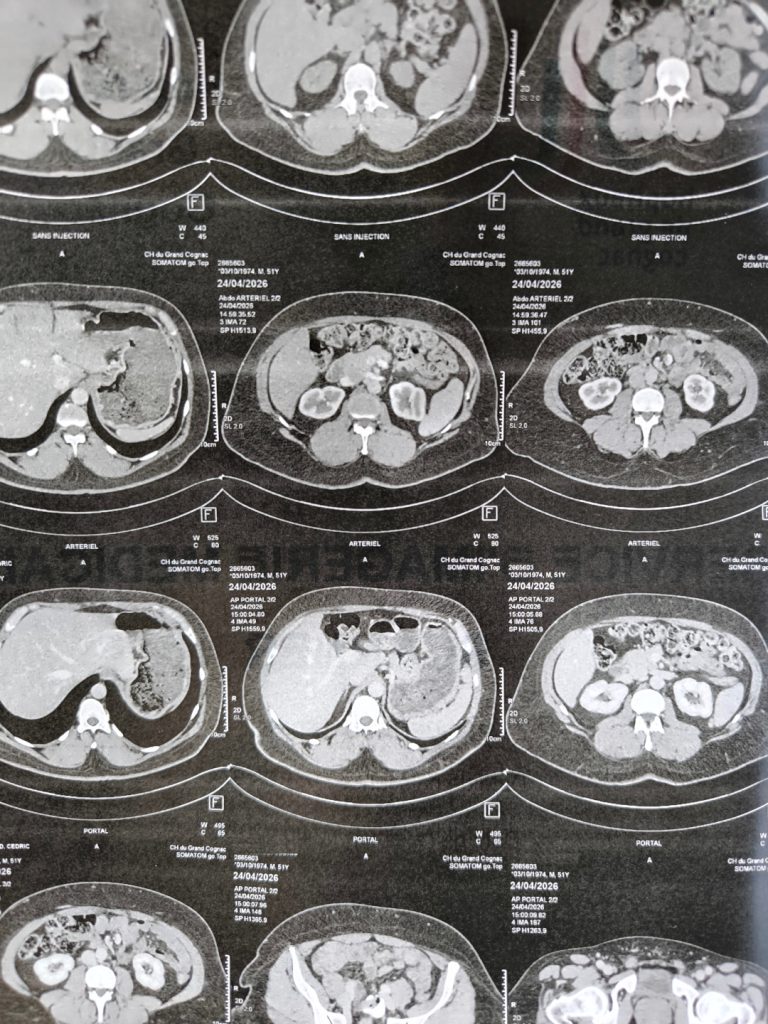

And then the nurse showed me the pictures, and I forgot all about the anti-climax.

I don’t understand how anyone looks at a cross-section of their own body and feels nothing. There it all was, organs I’d only ever encountered in textbooks, laid out in greyscale like some impossible map. And they were mine, not an abstract photo. You’ve been living inside this thing your whole life without ever having seen it from the outside, or from any angle at all really, and suddenly there it is. I found it completely gripping.

That curiosity is the closest I get to the version of myself that chose medicine. Asking too many questions during consultations. Finding a technician willing to geek out for a few minutes. Staring at images of my own pancreas and wanting to understand every shadow in the picture.

The scan came back clear, by the way. Yay!